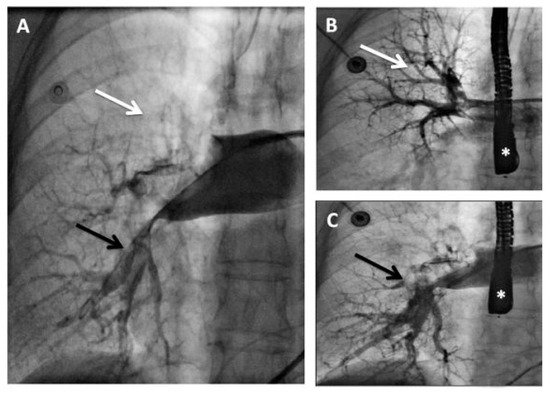

The percutaneous AngioJet™ rheolytic thrombectomy was rapidly and successfully performed at the pulmonary level (Figure 3), and the procedure was interrupted immediately when the haemodynamic condition of the patient had improved with elevation of systemic pressure permitting a diminishing dose of vasopressors. Due to the estimated high risk of dislodgement or fragmentation with subsequent systemic embolisation, the thrombus at the level of the PFO was not approached. The patient left the cardiac catheterisation laboratory under full heparin anticoagulation with stable haemodynamic conditions. Over a few hours, a progressive weaning from the vasopressor was possible and a second TEE performed 12 h following the procedure confirmed the improvement of the right ventricular function in the absence of residual intra-atrial thrombus. Without any further neurologic deterioration, the patient could be extubated on day 7 and she could be discharged from the hospital on day 60 with only mild neurological sequelae. At 12 months, she was still doing well without relapse on oral anticoagulation.

Figure 3. Pre-thrombectomy pulmonary angiogram (AP view): (A)Extensive thrombus occluding the right superior and middle lobar arteries (white arrow) and severely impairing flow in the inferior lobar artery (black arrow). After AngioJet™ Rheolytic Thrombectomy pulmonary angiogram (AP view): (B) Selective injection showing a near normal perfusion in the right superior and middle arteries (white arrow). (C)Selective injection showing an improved perfusion in the inferior lobar artery (black arrow). * Trans-oesophageal echocardiography probe.